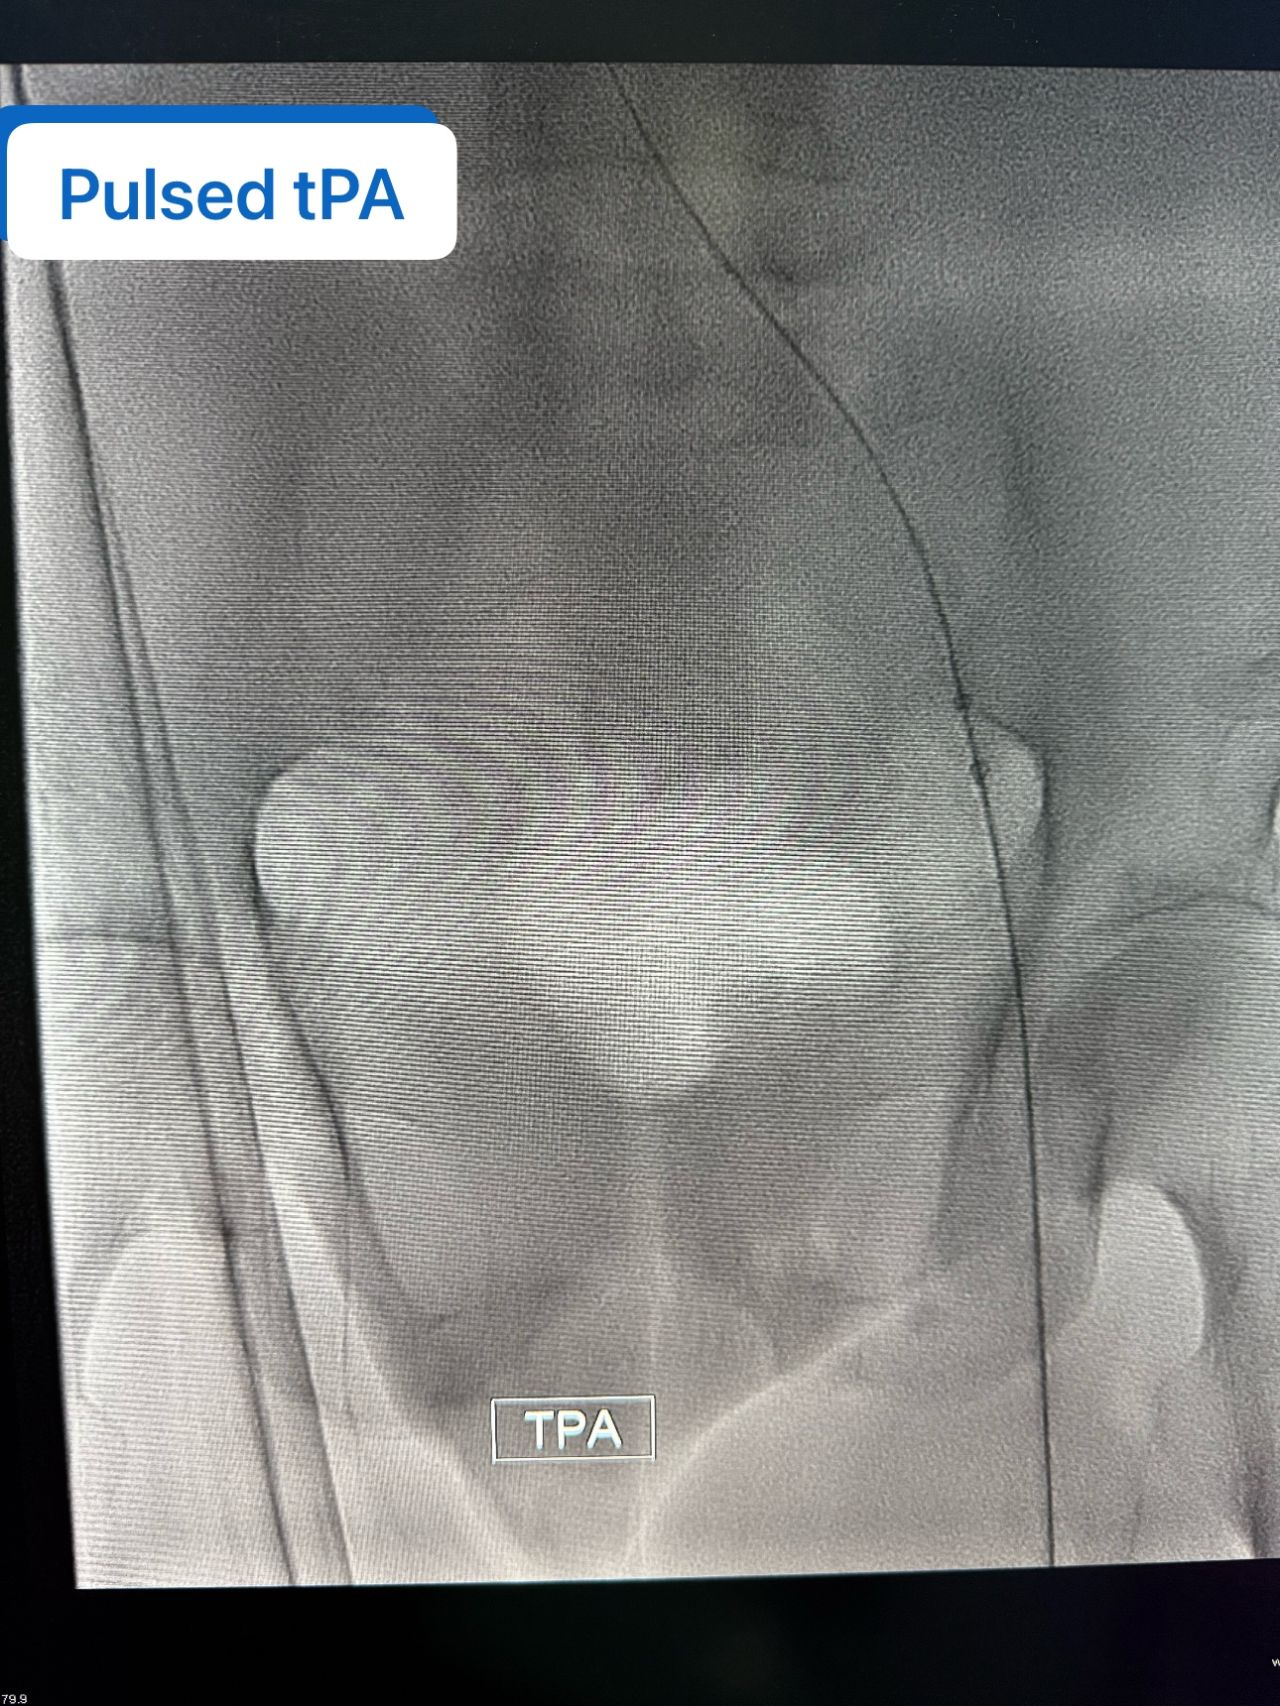

”Success Story | Advanced Interventional Care for DVT

We recently treated a 68-year-old female patient who developed a provoked deep vein thrombosis (DVT) following a left femur fracture—a common but potentially serious complication in immobile patients.

Given the extent of the clot burden and the patient’s clinical condition, we proceeded with a mechanical thrombectomy using the Angio Jet system.

The procedure was performed safely and efficiently, allowing us to restore venous flow, relieve symptoms, and prevent long-term complications such as post-thrombotic syndrome.

• Successful clot burdens reduction

• Immediate improvement in limb perfusion

• Smooth post-procedure recovery

• Patient discharged with optimized anticoagulation and follow-up plan

This case highlights the value of modern endovascular techniques in managing complex vascular conditions, even in elderly patients.